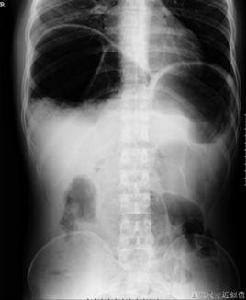

間位結腸綜合症也稱為Chilaiditi 綜合症,此症中右結腸曲嵌入肝臟與橫膈之間,其原因並非在腸管本身,肝臟的下垂和和位置異常是形成本病的基礎。常因肝臟的韌帶過長,薄弱、缺無等發育異常,使肝臟下移並與膈肌之間的間隙增寬,以至結腸嵌入之間形成本病。膈肌的先天薄弱或膈肌麻痹為本病的促發因素。此外在部分肝硬化患者中因右肝葉萎縮明顯,肝膈間隙增大也可見此症。

診斷

本病的診斷主要是X線與CT,現在也用超音波檢查。因部分氣體影響,超聲檢查也有它的局限性!